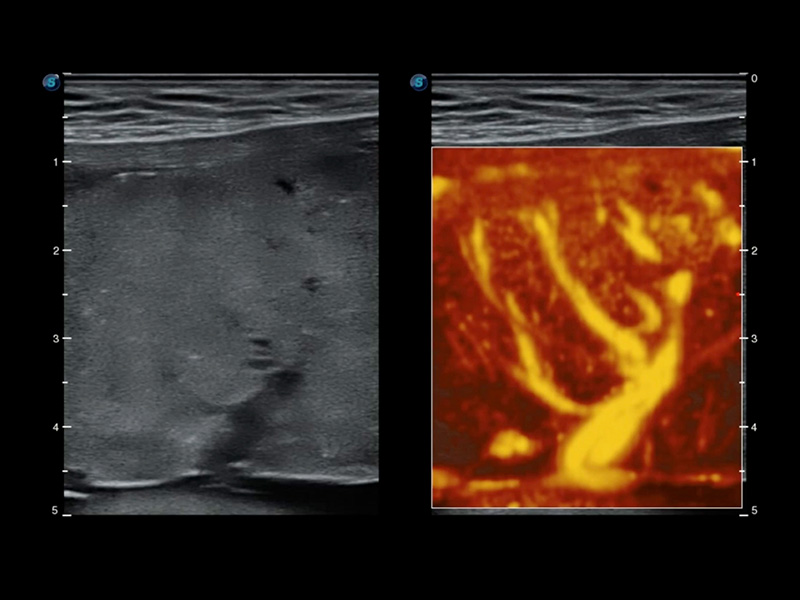

Micro F

Consente la visualizzazione delle strutture microvascolarizzate

Micro F offre un metodo innovativo per ampliare la portata di flusso visibile nell'ecografia, in particolare per visualizzare l'emodinamica dei piccoli vasi a flusso lento. Grazie all'adozione di un filtro adattivo avanzato e all'accumulo di segnali temporali e spaziali, Micro F è in grado di distinguere in modo efficace il flusso minuto dal movimento di tessuto sovrapposto e di rappresentare l'emodinamica con sensibilità e risoluzione spaziale più elevate.

• Arteria pericallosa fetale con Micro F

• Flusso ematico renale con Micro F

• Nodulo tiroideo con Micro F

• Linfonodo cervicale con Micro F